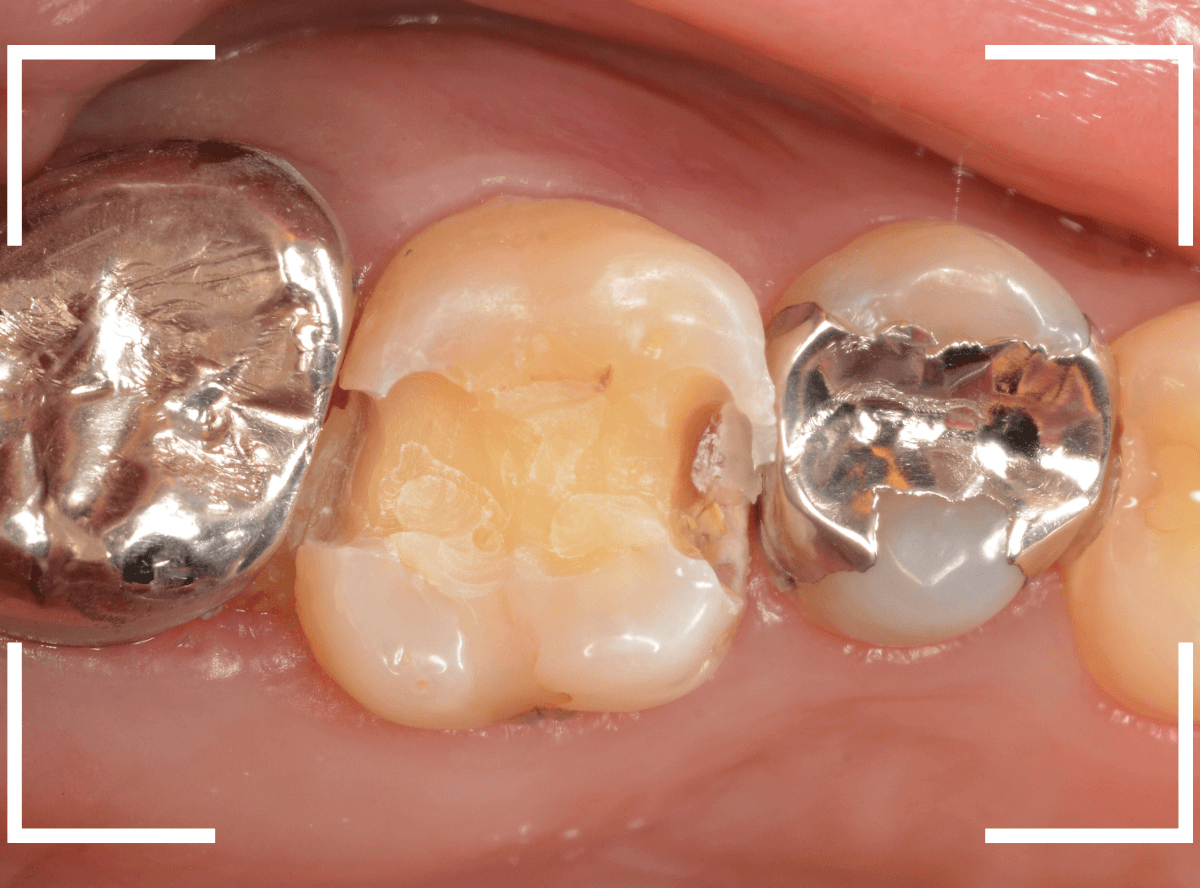

Case.18 虫歯なのは間違いないが、境界がはっきりしない

「つめものが外れて、噛むと痛い」という訴えで来院された患者さんさんです。

一見で、表面が虫歯になっているのと、レジンが劣化しているのがわかります。

レントゲン写真で確認します。

〇部が当該の歯です。

症状もあるので、虫歯が深そうですが、全体がもやっとして、どこからどこまで虫歯なのかはっきりわかりません。

まれに、こんな時もあります。

レジンを外し、虫歯の処置を進めます。

慎重に虫歯を除去し、一安心か、という寸前で(〇部、小さく出血しているところ)露髄してきました。

神経を除去しないとダメかもしれません。。。

神経を保護するお薬をつめて、経過観察します。

痛みが出ませんように。。。